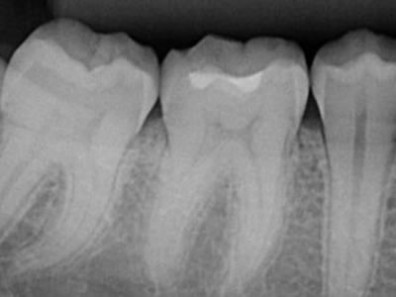

Radiografias Periapicais

Radiografia obtida através de uma técnica radiográfica intrabucal que tem como objetivo visualizar a anatomia dentária e estruturas adjacentes com a maior fidelidade dimensional e maior detalhamento das estruturas possíveis.